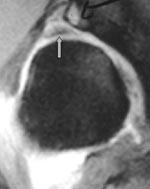

Tabell 1 viser våre funn. Labrum ble tydelig fremstilt på alle MR-artrogrammene. Normal labrum er triangulær i tverrsnitt og med lavt signal. Den er tynnere anteroinferiort og tykkere posterosuperiort. Nedad går den sammen med ligamentum transversum. Den perilabrale recess sees normalt superiort hvor leddkapselen hefter seg noen millimeter over øvre del av labrum (fig 2). Denne recess er mye mindre anteriort og posteriort.

Degenerativ labrum viste økt signalintensitet i labrum uten affeksjon av overflaten med inntakt recess hos to pasienter (fig 3) og med manglende fremstilling av recess hos tre pasienter (fig 4). Sistnevnte ansees forårsaket av labrumhypertrofi. Labrumruptur ble diagnosisert hos ti pasienter. Ruptur ble beskrevet når man kunne identifisere kontrast mellom labrum og acetabulum (fig 5) eller imbibering av kontrast i labrum (fig 6). Alle rupturene satt i øvre del av labrum.To av disse pasientene er operert, og vårt funn ble verifisert. Begge var aktive fotballspillere, og de hadde henholdvis stadium 2B og stadium 3B ved MR-artrografi. Dette samsvarte med de artroskopiske funn. Den tredje pasienten som er operert, viste forandringer forenlig med villonodulær synovitt. Også dette ble verifisert ved artroskopi (fig 7).